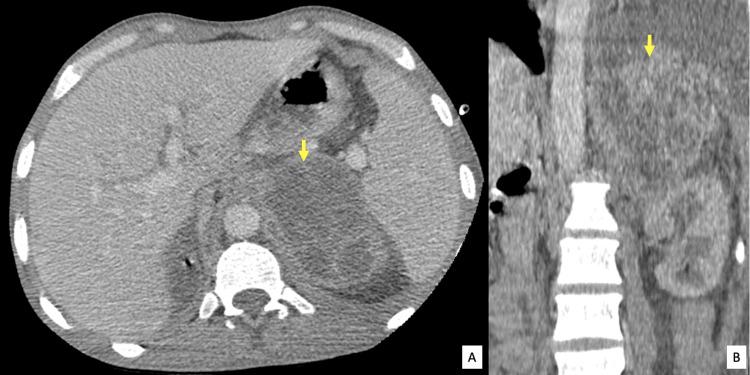

Adrenal gland abscesses are rare lesions usually reported to be caused by fungal pathogens and typically through hematogenous spread from other primary sources of infection. Imaging has always been known to play a major role in the characterization of focal adrenal lesions. However, given the rare occurrence of abscesses in this location, making the right diagnosis remains challenging. We report the case of a 39-year-old man with chronic renal disease on hemodialysis presenting with signs of sepsis and left upper quadrant pain revealing a left adrenal gland abscess.

肾上腺脓肿是罕见的病变,通常据报道是由真菌病原体引起的,并且通常是通过血行播散来自其他原发性感染源。影像学一直被认为在局灶性肾上腺病变的特征性诊断中起主要作用。然而,鉴于该部位脓肿的罕见性,做出正确诊断仍然具有挑战性。我们报告了一例39岁接受血液透析的慢性肾病男性患者,其出现败血症体征和左上腹疼痛,检查发现左侧肾上腺脓肿。